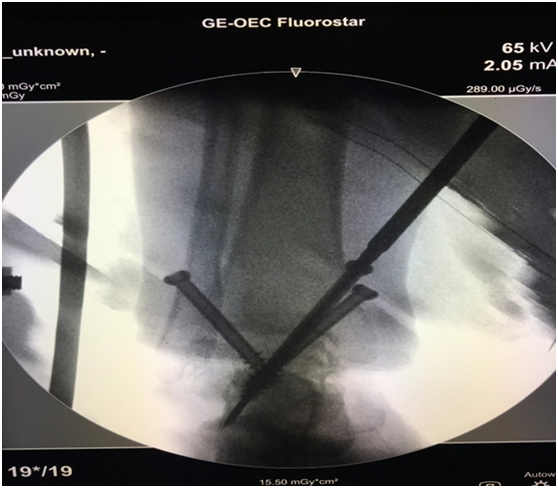

術(shù)中完美置釘融合